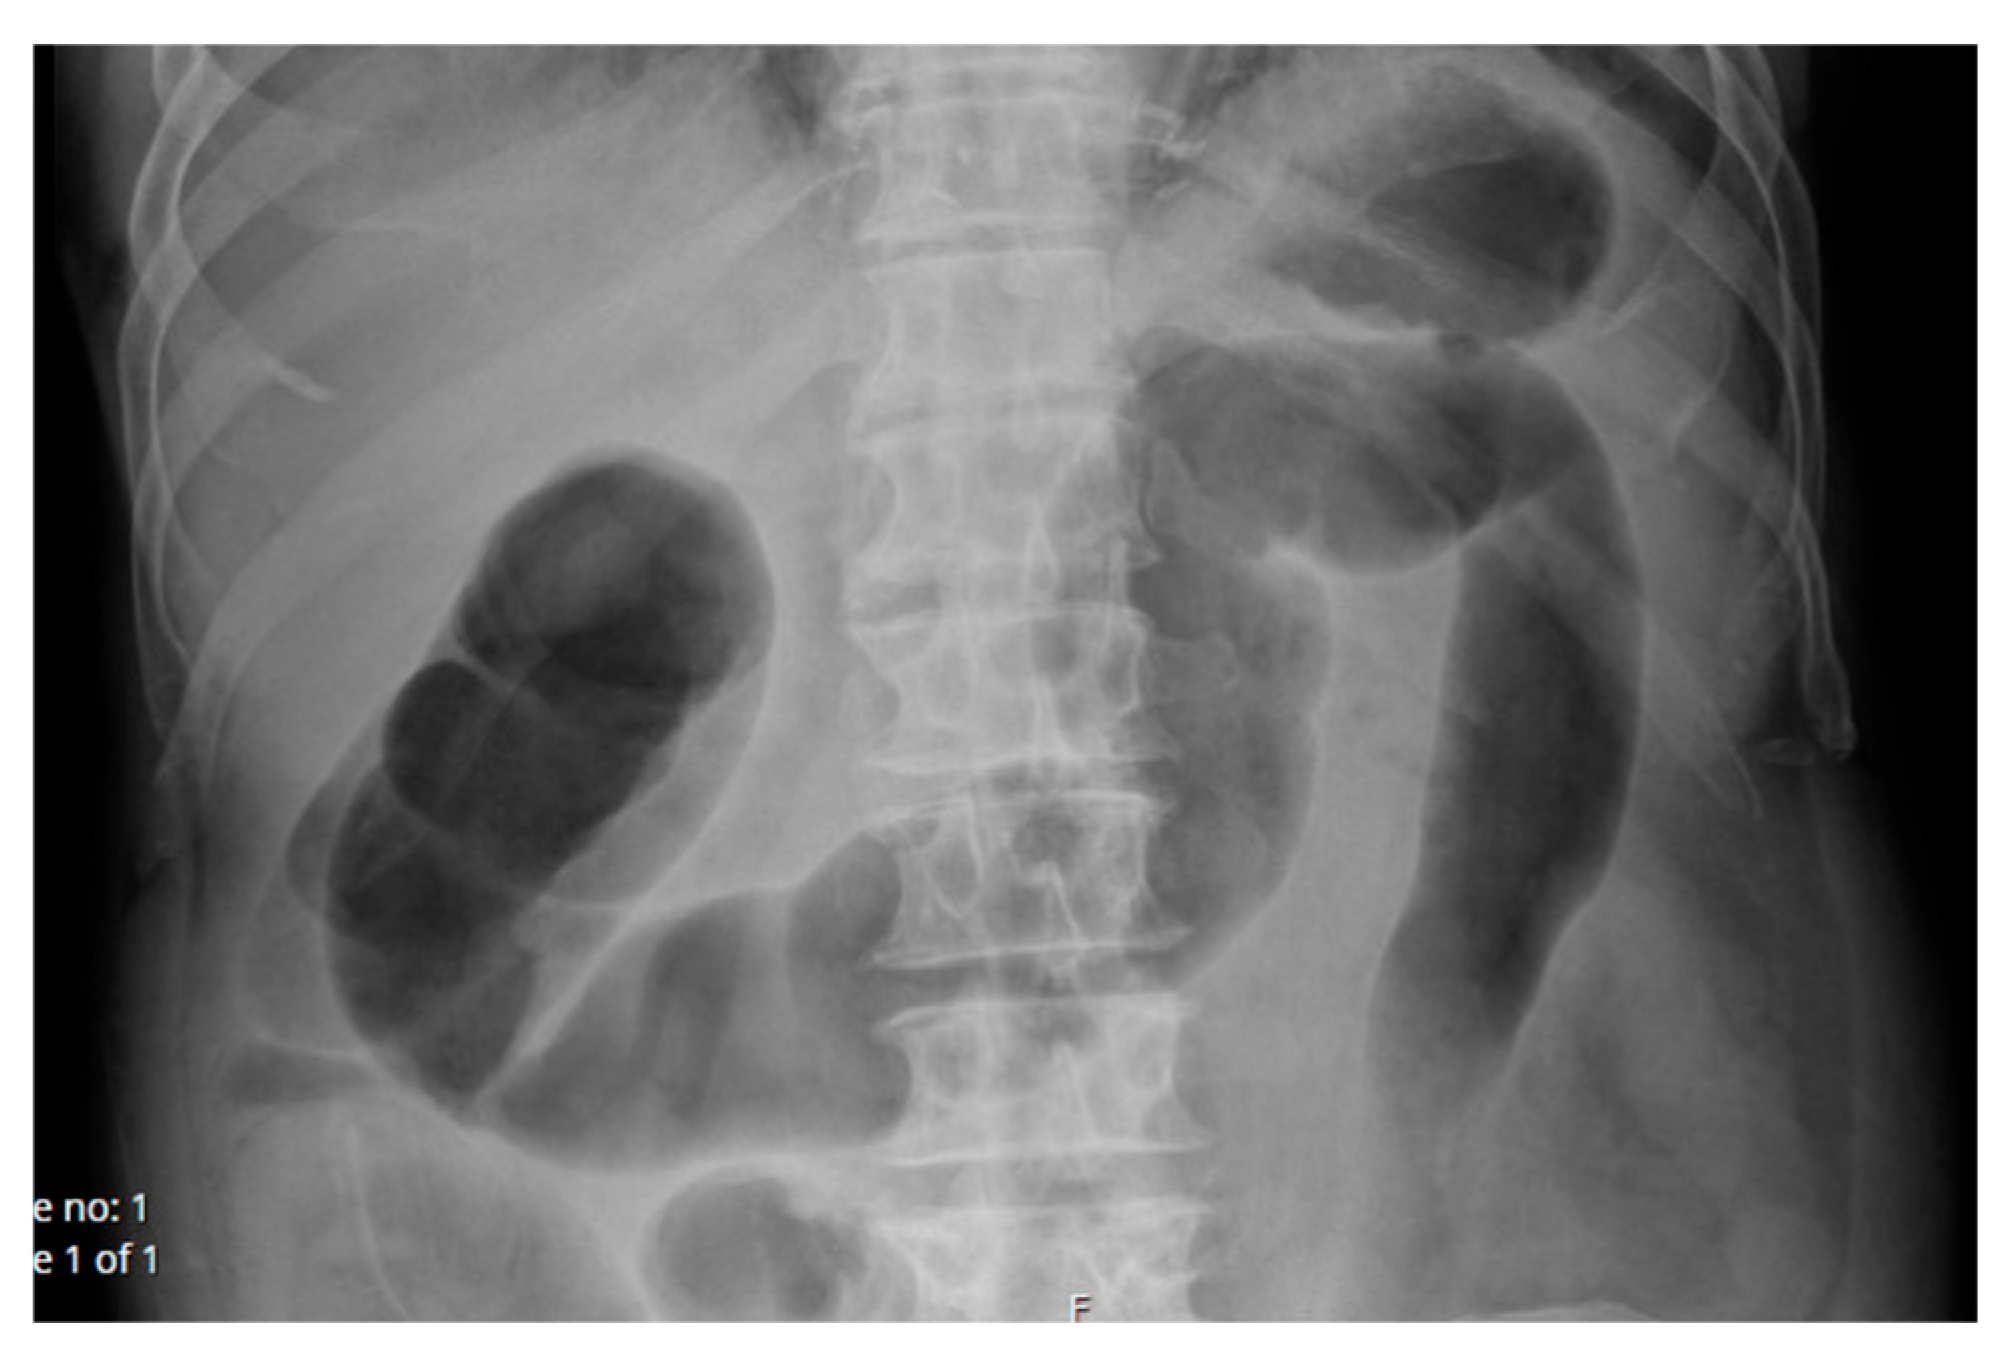

2.1.1. Case 1

2.1.2. Case 2